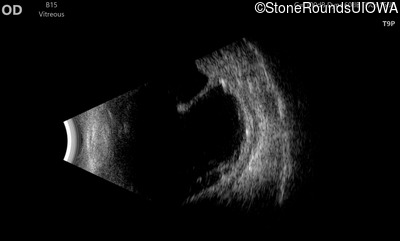

B-Scan Ultrasonography - Left - 20/300

Exemplar